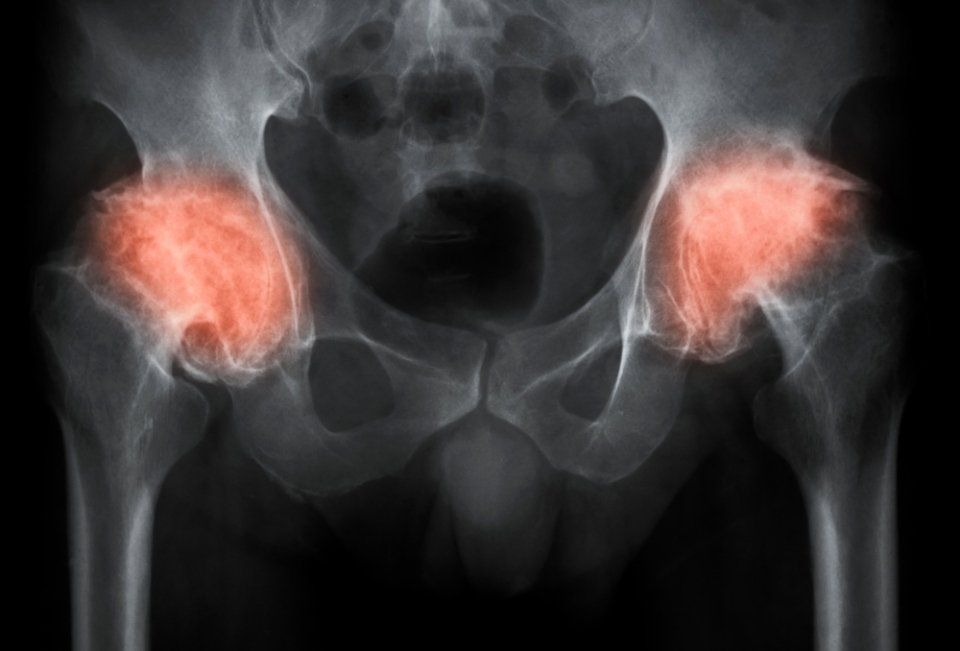

L’osteoporosi è una patologia che colpisce principalmente le donne, manifestandosi soprattutto con l’avanzare dell’età. Consiste in una progressiva riduzione del calcio e della massa ossea, con gravi conseguenze sulla mobilità e un crescente rischio di fratture che riguardano più spesso polso, anca o vertebre.

L’osteoporosi può essere affrontata senza troppe complicazioni: per questo motivo, esami di controllo periodici vengono spesso suggeriti dai medici.